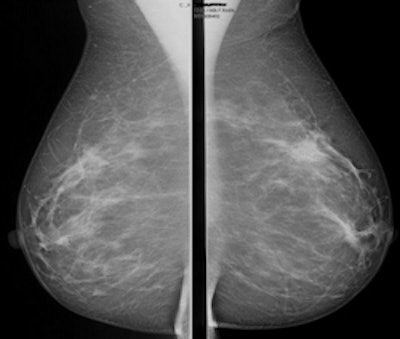

A 56-year-old woman without a family history of breast cancer had a negative screening mammogram. MRI screening revealed a large, nonpalpable breast cancer in the immediate retro-areolar region of the left breast readily picked up by the maximum intensity projection (MIP) image (below). All images courtesy of Dr. Christiane Kuhl.

These two first postcontrast subtracted (FAST) images are from the same patient.